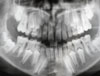

לאחר ההשחזה נלקחות מידות ע"י הטבעת תבנית השיניים בחומר מיוחד (במרפאות מסוימות ישנה סריקת מידות ממוחשבת). התבנית נשלחת למעבדת שיניים, שם מיוצר בסיס כתר המתכתי (בכתרים עם בסיס מתכת) או כתר סופי (בכתרי חרסינה בלבד או מתכת בלבד). במקרה של כתרים העשויים חרסינה, הרופא בוחר בשלב זה את צבע הכתר המיועד בהתאם לצבע השיניים הטבעיות.